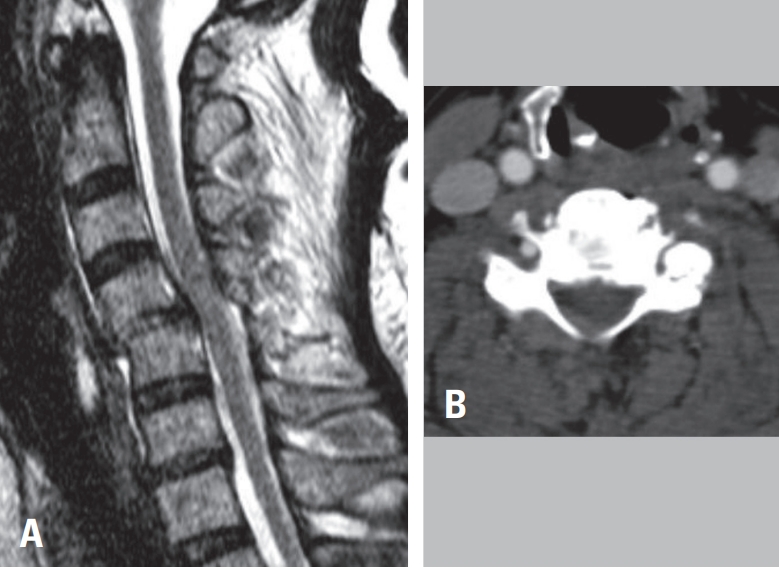

Fig. 1B). Magnetic resonance imaging showed spinal cord compression at C4–C5 with corresponding intramedullary signal change (

Fig. 1C).

To evaluate for vertebral artery injury secondary to facet dislocation, neck CT angiography was performed, confirming occlusion of the left vertebral artery at C4–C5 (

Fig. 1D). As there were no acute posterior circulation symptoms, the patient underwent urgent anterior cervical discectomy and fusion (ACDF) at C4–C5 to relieve cord compression (

Fig. 1.

(A) Lateral cervical spine radiograph demonstrating traumatic anterior translation at C4–C5. (B) Cervical spine CT showing left C4–C5 facet dislocation. (C) Cervical spine MRI revealing spinal cord signal change at the C4–C5 level. (D) Neck CT angiography demonstrating occlusion of the left vertebral artery at C4–C5 secondary to facet dislocation.